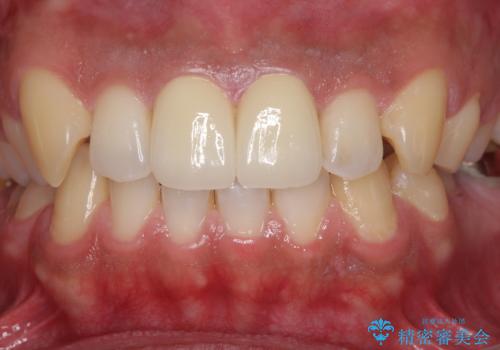

捻れた出っ歯の前歯 オールセラミッククラウンによる審美治療

1度の来院で進められる限りの処置を行ったため、4回の来院で僅か1ヶ月で治療を終えることができました。

気になっていた前歯の問題が解決し、患者様には大変満足していただきました。